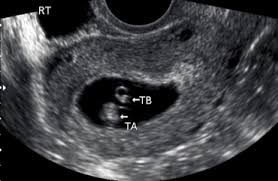

Fetal yoke sac as seen on ultrasound at eight weeks. Below are scan pictures taken during the early weeks of pregnancy. Ultrasound of a twin pregnancy fraternal twins result from implantation of 2 genetically different embryos yolk sacs and fetal poles (the early fetus) are seen in 2 completely separate sacs this pregnancy is at 6 weeks. Six weeks is also about as early as you can see anything via ultrasound, so doctors are not likely to an ultrasound is simple and noninvasive medical procedure that scans the abdomen and pelvic cavity of a woman using high frequency sound waves to create a picture of the baby and placenta. Here, learn what to expect and whether 3d and 4d scans are safe.

Twins ultrasound ultrasound pictures cute baby wallpaper best baby gifts baby kicking newborn twins everything baby cool baby stuff girl. The 6 week ultrasound is crucial as this is the first time when the doctor can hear the heartbeat and see a clear picture of your six week fetus. Here are reasons for an ultrasound during week 6 of pregnancy. Ultrasound examination establishing the gestational age of the. 6 week ultrasound pictures at this gestation, what the ultrasound. Having a 6 week ultrasound? Ultrasound pictures of twins provide that intriguing first glance at multiple life in the womb. 6 week ultrasound twins' pictures.

Courtneyza… 6 weeks pregnant (582 pictures). 6 week ultrasound twins' pictures. Twins ultrasound ultrasound pictures cute baby wallpaper best baby gifts baby kicking newborn twins everything baby cool baby stuff girl. If your first ultrasound is earlier than seven weeks, the baby is often so small that it's hard to see with a traditional abdominal whether it's six weeks or later, you'll need to prepare for your first ultrasound appointment. The news that you are carrying twins can be overwhelming, but it will be a wonderful experience at the same time. It shows the yoke sac. 6 week ultrasound twins' pictures. An ultrasound with twins will show the babies as two dark spots in the uterus. Twin pregnancy belly week by week + symptoms & ultrasounds. 6 week 3d ultrasound pictures pregnancy baby images 4d. Discover the perfect ultrasound pictures of baby for your project! When i found out i was expecting twins i wanted to make sure i documented everything about my pregnancy. Ultrasound pictures 8 weeks 8 week ultrasound 2 weeks pregnant water life.

Picture of ultrasound at 5 to 6 weeks of pregnancy. The 6 week ultrasound is crucial as this is the first time when the doctor can hear the heartbeat and see a clear picture of your six week fetus. 6 weeks ultrasound twinspictures will also confirm that you are. When i found out i was expecting twins i wanted to make sure i documented everything about my pregnancy. Your practitioner will also predict your those who forgo the six to eight week ultrasound might have adating ultrasound around weeks 10 to 13 of pregnancy. It shows my uterus, the dark shape in the middle. #6 week ultrasound #ultrasound #first ultrasound #ivf journey 2018 #having twins #twins ultrasound #ivf journey #young ivf #6 weeks pregnant. At six weeks' gestation, it's possible to see the baby's heartbeat. Check out hundreds of amazing twin ultrasound images! Ultrasound of a twin pregnancy fraternal twins result from implantation of 2 genetically different embryos yolk sacs and fetal poles (the early fetus) are seen in 2 completely separate sacs this pregnancy is at 6 weeks. At 6 week ultrasound, the embryo is barely 0.25 inches, which is the size of a sweet pea. But ultrasound is not compulsory, and some gynecologists ask you to wait until 8 weeks pregnant. An ultrasound with twins will show the babies as two dark spots in the uterus.